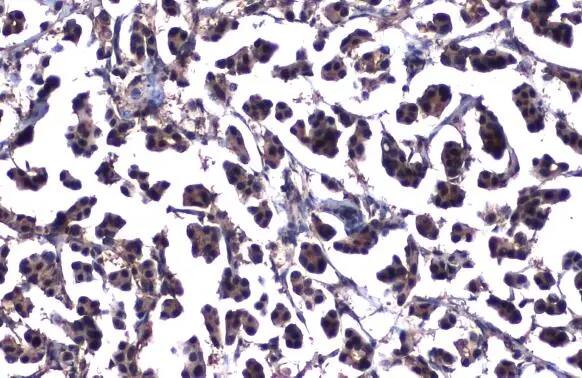

Immunohistochemistry-Paraffin: ATM Antibody (2C1-RB) [NBP3-13655] -

Immunohistochemistry-Paraffin: ATM Antibody (2C1-RB) [NBP3-13655] - ATM antibody [2C1-RB] detects ATM protein at nucleus by immunohistochemical analysis.

Sample: Paraffin-embedded human breast carcinoma.

ATM stained by ATM antibody [2C1-RB] (NBP3-13655) diluted at 1:200.

Antigen Retrieval: Citrate buffer, pH 6.0, 15 min